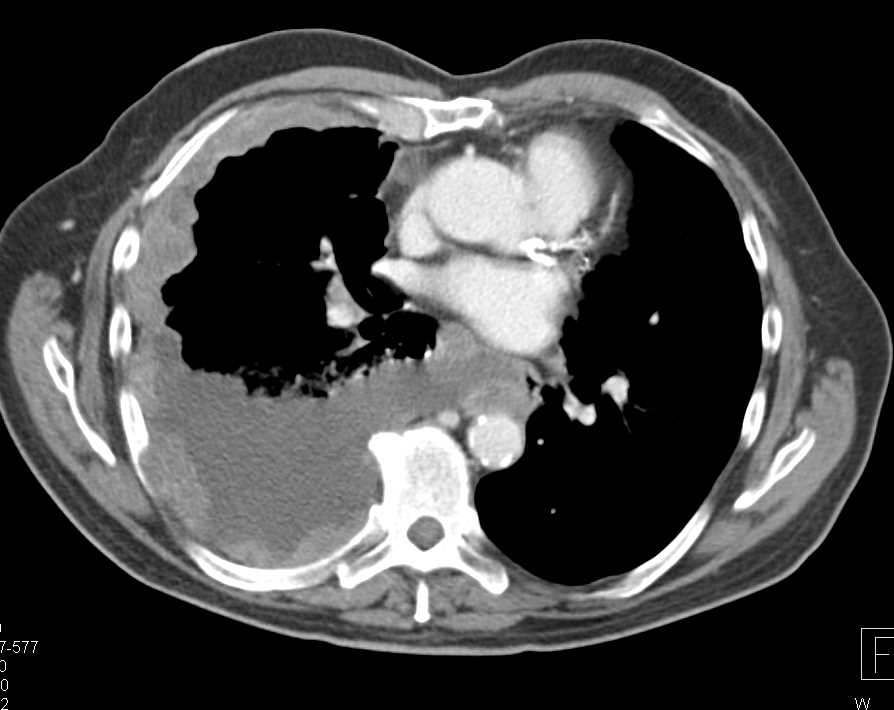

Pulmonary Arteriovenous Malformation (AVM) in 3D